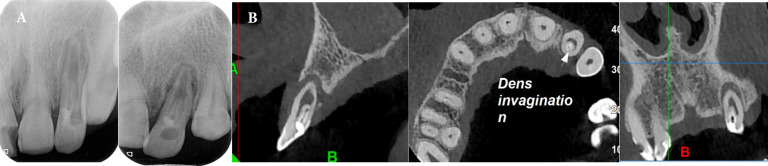

Endodontic treatment in dens invaginatus anomaly is associated with challenges in all stages. This case report outlines the therapy provided for tooth #10 with occasional pain. In examinations, tenderness to percussion and touch and non-response to sensibility tests were observed, and pulp necrosis and symptomatic periapical periodontitis were diagnosed. Radiographic evaluation showed a structural anomaly related to the dens invaginatus and the associated periapical lesion. Cone-beam computed tomography confirmed the presence of DI type II. Endodontic treatment combined with photodynamic therapy and active irrigation using a dental operating microscope was successful and radiographic examinations showed periapical healing along with bone formation in 6-month and 1-year follow-ups.